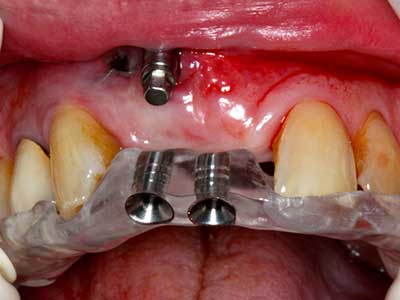

Si es preciso realizar intervenciones quirúrgicas en las que el hueso está en contacto directo con estructuras sensibles, como son los vasos sanguíneos o los nervios, los instrumentos rotativos presentan un enorme potencial de provocar lesiones iatrogénicas. Así, precisamente en la representación de nervios después de una lesión iatrogénica, o en el transcurso de la lateralización de un nervio para resecciones, reconstrucciones o incorporación de implantes, los equipos piezoeléctricos pueden resultar muy útiles para preparar la tapa ósea y retirar las partes de tejido duro cercanas al nervio (fig. 17-20). Por lo general, un ligero contacto del cordón nervioso con el inserto piezoeléctrico no tiene consecuencia alguna; ahora bien, un procedimiento poco cuidadoso con movimientos tipo sierra o piezas de trabajo sobre la base ósea aún existente puede provocar lesiones nerviosas temporales o incluso permanentes. Con todo, el riesgo de sufrir una lesión de este tipo se considera significativamente inferior que en los casos en los que se utilizan sierras y fresas (Pereira, Gealh et al. 2014).

Aplicación: Terapia periodontal